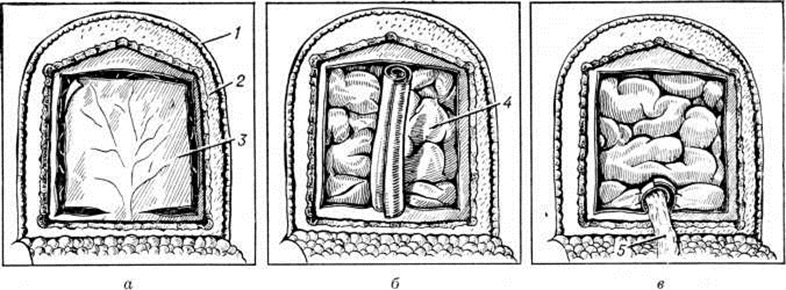

Одним из универсальных методов лечения гидроцефалии является операция Кюттнера — Венгловского. Гидроцефалия Кюттнер предложил вскрывать полость переднего рога бокового желудочка и создавать отток цереброспинальной жидкости из желудочка в субдуральное, эпидуральное пространства и подкожную клетчатку черепа. В последующем наряду со вскрытием он вводил в полость желудочка уплотнённую артерию, обшитую двумя языкообразными лоскутами, выкроенными из твёрдой мозговой оболочки. Р. И. Венгловский в качестве дренажа применил лоскут из твёрдой мозговой оболочки вместе с питающим его сосудом, свёрнутым в виде трубочки (рисунок 11). Хотя операцию автор выполнил в 1907 г., первые сообщения он сделал только в 1913 и 1917 годы. С. Л. Колюбакин (1923) заменил трубочку из твёрдой мозговой оболочки лоскутом, выкроенным в виде буквы «Т». А В. Н. Розанов (1926) предложил при этой операции зашивать твёрдую мозговую оболочку, предварительно расщепленную по Н. Н. Бурденко.

Операции при арезорбтивной гидроцефалии. Наиболее широкое распространение получила операция люмбо-перитонеального отведения цереброспинальной жидкости, при которой жидкость из субарахноидального пространства спинного мозга на уровне LIII-IV с помощью трубки дренируется в брюшную полость.Оментодуральный анастомоз по Бурденко — Бакулеву (рисунок 10) — операция, направленная на отведение цереброспинальной жидкости из субарахноидального пространства в брюшную полость. Для этого из сальника иссекают лоскут длиной около 15 сантиметров, основание которого имеет хорошо сохранённое кровоснабжение.